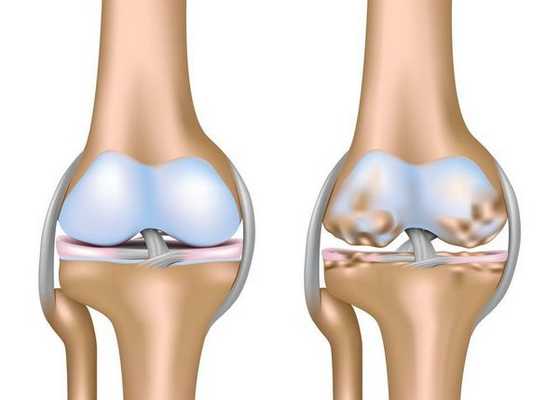

Артроз коленного сустава (гонартроз) — это прогрессирующее хроническое заболевание коленных суставов с повреждением, истончением и разрушением его хрящевой части (суставные поверхности бедренной и большеберцовой костей), а также поражением субхондральной кости. [2] [5] [16] Доказано исследованиями (артроскопия и МРТ), что помимо поражения суставного хряща в процесс вовлекаются мениски и синовиальная оболочка. Гонартроз — одна из самых распространенных ортопедических патологий. [4] [6] [9] [22] Существуют его синонимы — остеоартроз (ОА), деформирующий артроз. Заболевание является важной социально-экономической проблемой, так как широко распространено и значительно ухудшает качество жизни больных из-за постоянного болевого синдрома и, кроме того, становится причиной высокой инвалидизации. [15] [27]

До середины восьмидесятых годов прошлого века не было унифицированного определения заболевания. Только к 1995 году комитетом по остеоартрозу Американского колледжа ревматологии заболевание было охарактеризовано как результат действия механического и биологического факторов, приводящих к дисбалансу между процессами деградации и синтеза внеклеточного матрикса суставного хряща. [11] [19] В итоге происходит его разволокнение и дегенерация, образуются трещины, остеосклероз и уплотнение кортикального слоя субхондральной кости, растут остеофиты и формируются субхондральные кисты. [12] [29]

Деформирующий остеоартроз - частая патология суставов, при которой нарушение регенерации соединительнотканных структур приводит к преждевременному старению суставного хряща - его истончению, шероховатости, растрескиванию, потере прочности и эластичности. Субхондральная кость обнажается и уплотняется, в ней происходят остеосклеротические изменения, образуются кисты и краевые разрастания - остеофиты.